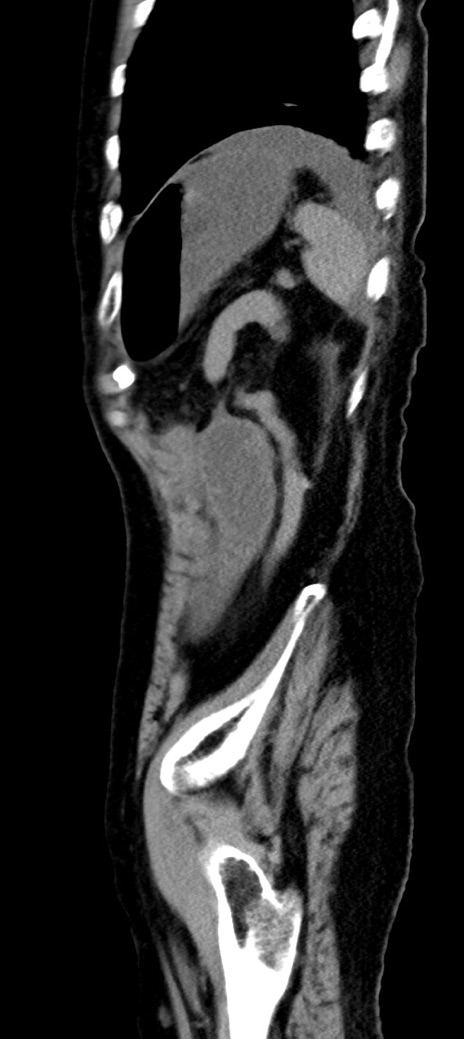

横断像

冠状断像

他院CT